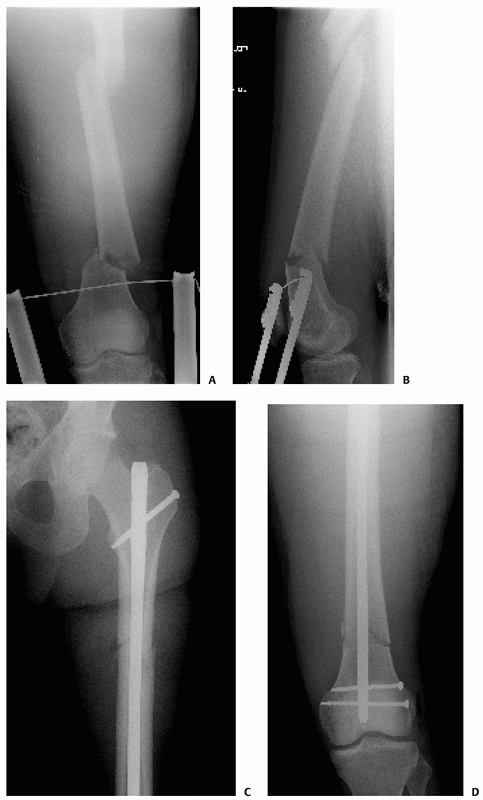

![]() |

FIGURE 50-10 Femoral plating for a simple fracture pattern. Plate length and screw position are more important than screw number.

FIGURE 50-11 This 74-year-old male sustained a periprosthetic femoral shaft fracture after a motor vehicle crash (A, B). He had no previous problems with his hip prosthesis. The femur was plated using an extensile lateral approach (C-F).

Given the spiral fracture configuration, a direct fracture reduction with lag screw fixation was performed. A long neutralization plate that spanned the entire femur was used. |